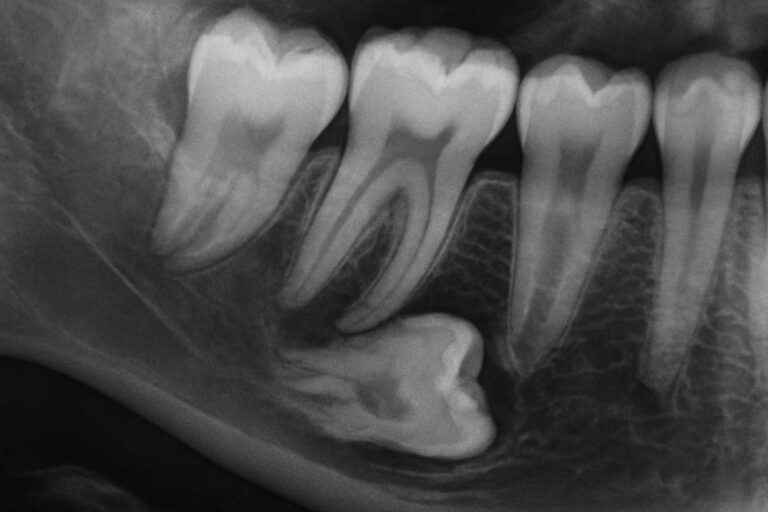

Wisdom teeth are the last set of molars to come in, usually between the ages of 17 and 25. For many people, these teeth cause pain because they erupt late into a jaw that may be too small, or they push against other teeth and gum tissue. A very common